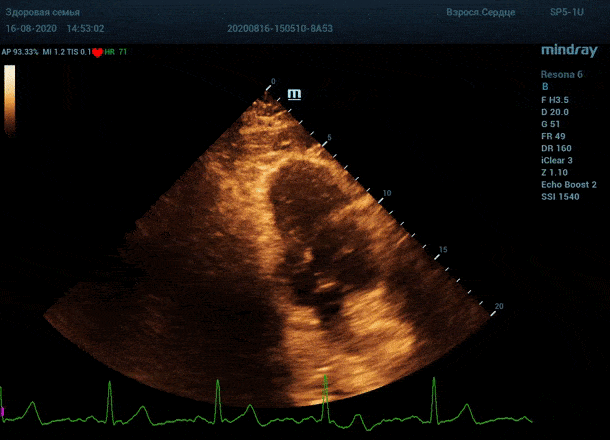

Глаз каждого человека по своей природе уникален. Одни люди лучше видят белый и серый цвет, прекрасно различают все его оттенки. Другим людям проще ориентироваться в голубом, синем и фиолетовом диапазоне, холодных тонах изображения. Однако большинство прекрасно видит оранжевый цвет, и очень четко отличает его от черного – анэхогенного пространства.

Адаптивный колорайзинг - настоящая находка для опытного врача ультразвуковой и функциональной диагностики. Для тренированного глаза открывается новый мир четких контуров, совершенно другой взгляд на привычные структуры сердца.